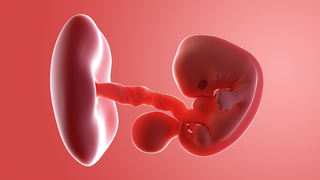

What does my baby look like?

Your baby, or embryo, is around 6mm long, which is about the size and shape of a pea. Some people think it resembles a tadpole with its little tail.

The arms and legs are starting to form and are known as limb buds. There are tiny dents where the ears will be.

There's a bump where the heart is and another bulge where the head will be. Sometimes the heartbeat can be picked up by a vaginal ultrasound scan, but you are unlikely to be offered one unless you've had IVF.

The embryo is covered with a thin layer of transparent skin.